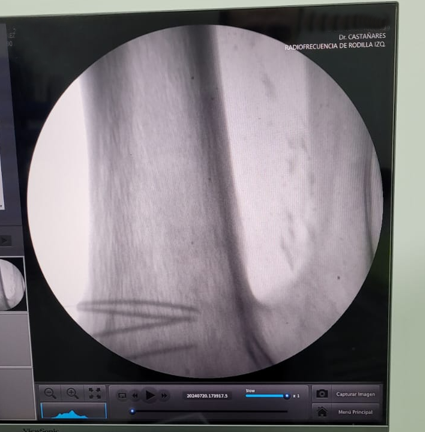

En Tidol tratamos el caso de un paciente de 90 años, con artrosis severa de rodilla izquierda.

El paciente presentaba limitaciones de reemplazo total de rodilla y no se le podía realizar la cirugía por osteoporosis y comorbilidad; por lo que se decidió realizar tratamiento con radiofrecuencia de los nervios geniculados.